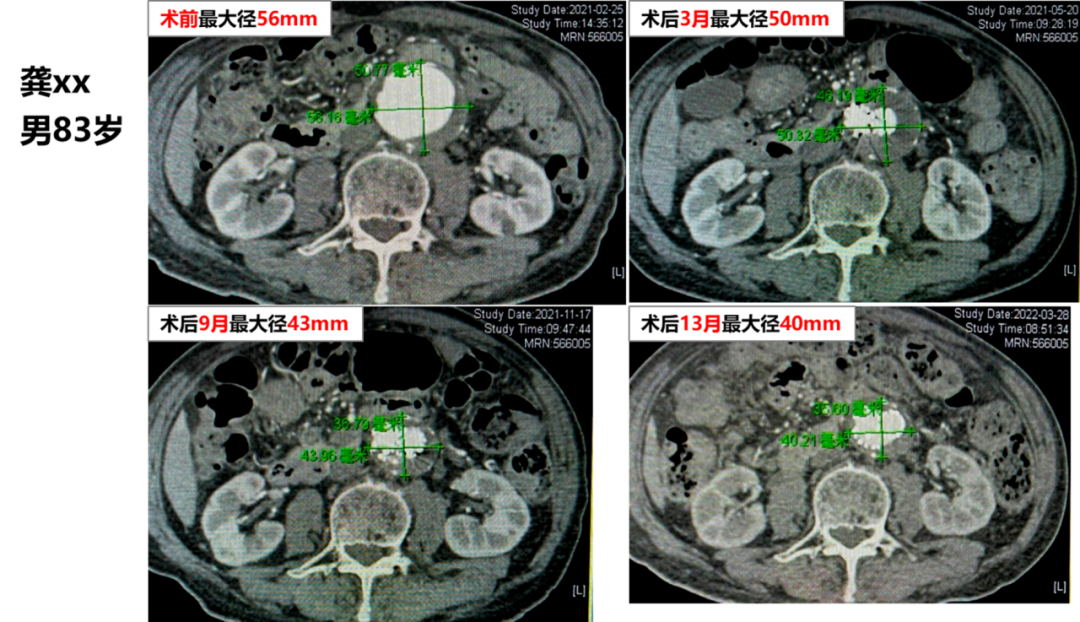

自 2018 年起,我院在 EVAR 术中常规 预置导管至瘤腔,释放支架后立即 注入凝血酶,诱导瘤腔内生理性血栓形成。

初步成果(70 余例随访):

II 型内漏发生率显著降低;

动脉瘤囊回缩速度明显快于传统组(1 个月即可见显著缩小,6 个月更明显);

无过敏、异位栓塞或感染等并发症(得益于严格操作质控)。